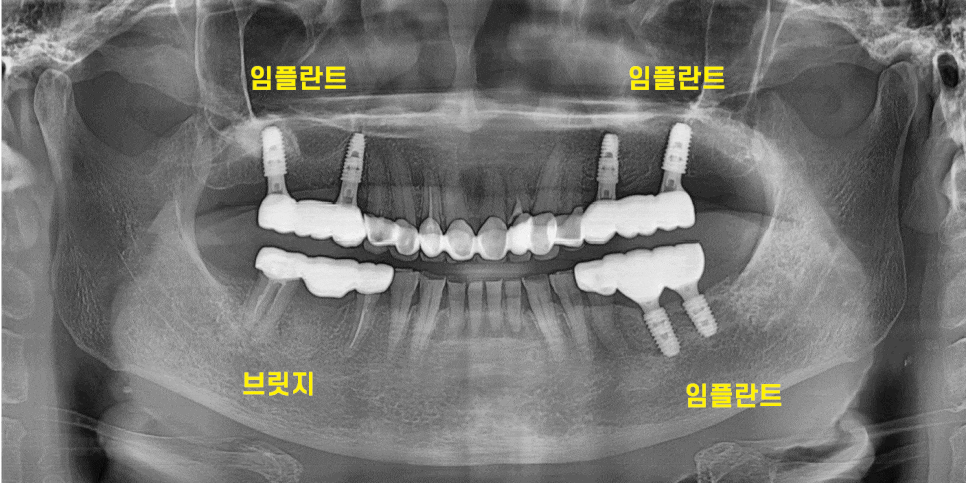

처음 오셨을때 윗니 어금니 6개가 빠져있었는데요.

양쪽 작은 어금니 1개로 식사를 하고 계셨습니다.

230526

오른쪽 위에 어금니는 치아가 없고

아래 어금니의 경우 염증으로 잇몸 뼈가 녹아있었는데요.

아래 치아의 경우 문제가 되는 부분만 1)임플란트를 한다.

- 브릿지 치료를 한다

2개의 선택지가 있었습니다.

각각의 장단점을 설명드렸고

브릿지 치료로 진행하기로 하였습니다.

문제가 되는 치아와 앞에 치아가 묶여 있어

잘라내서 새로 씌워줘야하고

맨 끝에 치아도 치료 후 보철이 필요하다보니

브릿지로 3개 한번에 씌우는 것을

선택해주셨습니다.